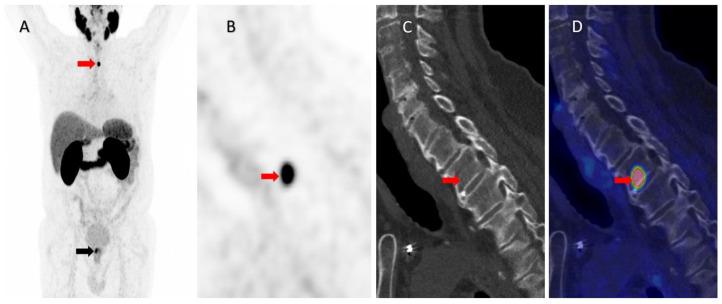

A 78-year-old man with newly diagnosed high-risk prostate cancer underwent Ga-PSMA PET/CT for primary staging. This showed a single, very intense PSMA uptake in the vertebral body of Th2, without discrete morphological changes on low-dose CT. Thus, the patient was considered oligometastatic and underwent MRI of the spine for stereotactic radiotherapy planning. MRI demonstrated an atypical hemangioma in Th2. A bone algorithm CT scan confirmed the MRI findings. The treatment was changed, and the patient underwent a prostatectomy with no concomitant therapy. At three and six months after the prostatectomy, the patient had an unmeasurable PSA level, confirming the benign etiology of the lesion.

一名78岁新诊断为高危前列腺癌的男性接受了镓-前列腺特异性膜抗原(Ga-PSMA)正电子发射断层扫描/计算机断层扫描(PET/CT)进行初步分期。结果显示在胸2椎体有单一、非常强烈的PSMA摄取,低剂量CT上无明显形态学改变。因此,该患者被认为是寡转移,并接受了脊柱磁共振成像(MRI)以进行立体定向放射治疗规划。MRI显示胸2椎体有非典型血管瘤。骨算法CT扫描证实了MRI的结果。治疗方案改变,患者接受了前列腺切除术,未进行辅助治疗。前列腺切除术后三个月和六个月,患者的前列腺特异性抗原(PSA)水平不可测,证实了病变的良性病因。